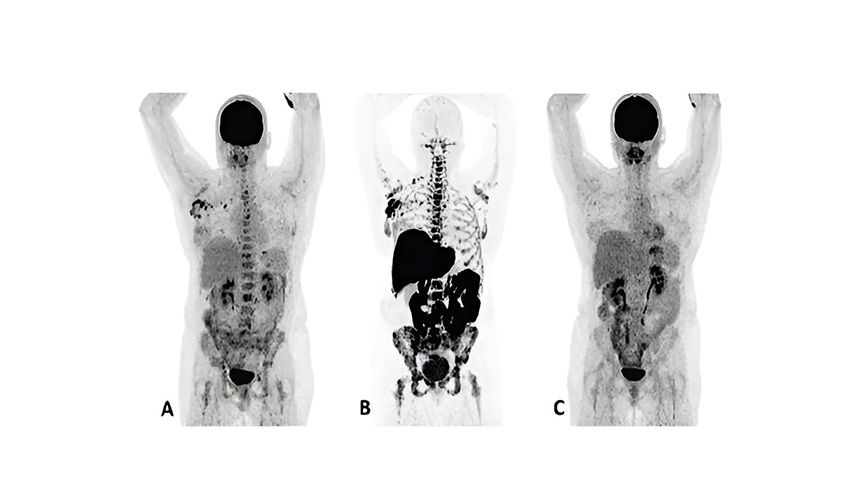

F18 fluoroestradiol and FDG PET images in a MBC treatment responder and non-responder*†⁶

Patient 1

(anterior/superior) responded to treatment with an AI and a CDK 4/6 inhibitor*6

†Upper row responder: Baseline FDG PET (A) showed pathological uptake in axillary lymph nodes (right side) and in nearly all vertebrae and pelvic bones. Image B showed the baseline F18 fluoroestradiol PET with pathological ER expression in the axial skeleton (including vertebrae, pelvic bones, proximal humeri and femora) and in axillary lymph nodes (right side). After 8 weeks, the FDG PET (C) showed almost complete metabolic response (just some slightly elevated uptake in the axillary lymph nodes). The patient had been on treatment for more than 70 weeks. Lower row non-responder: Baseline FDG PET (D) showed pathological uptake in multiple skeletal lesions. Image E showed the baseline F18 fluoroestradiol PET with only some increased ER expression in thoracic vertebrae. After 8 weeks, the FDG PET (F) showed no metabolic response, even some increase in the pathologic uptake in the multiple skeletal lesions6.

Images from a prospective, single center, feasibility study that aimed to explore whether baseline F18 fluoroestradiol PET discordance and F18 fluoroestradiol uptake were correlated with outcome and response to concomitant treatment with an AI and a CDK 4/6 inhibitor. Thirty patients with ER+ MBC were included in the study, including 87% who received at least one previous line of ET in the metastatic setting6.

*The F18 fluoroestradiol administered in this study was not equivalent to the FDA-approved formulation of Cerianna.